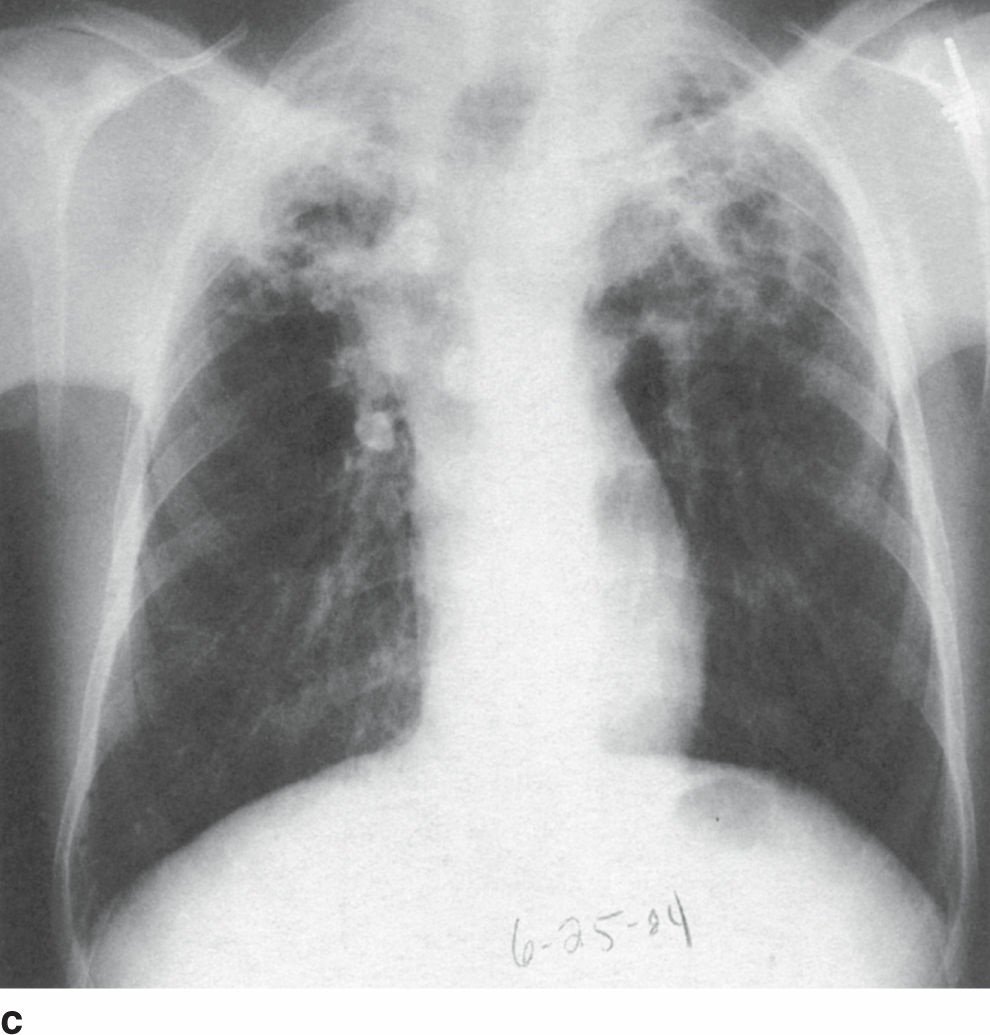

- Người lớn tuổi, ho đàm mạn tính kèm triệu chứng toàn thân như sốt nhẹ về chiều, mồ hôi đêm gợi ý lao phổi. Khám có ran nổ thùy trên và X-quang C cho thấy tổn thương kinh điển của lao: sẹo, xơ, và hang ở đỉnh và thùy trên phổi – đặc trưng của thể lao phổi tái hoạt.